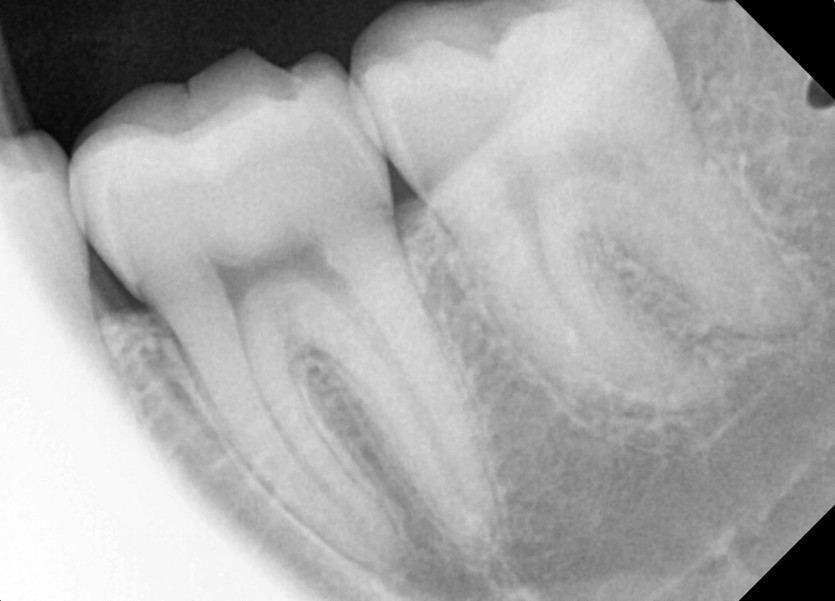

#28,38 사랑니 발치

구강 외과 전문의가 당일 발치했습니다.